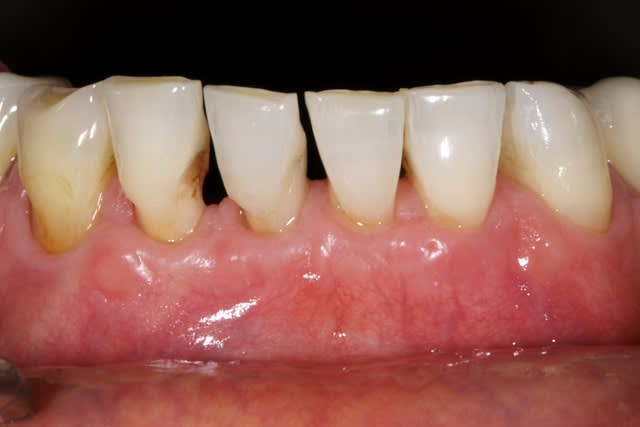

Je stressais pas mal sur ce cas quant à la réussite du conj. enf. avec lamb. tracté coronairement. Mais le résultat est acceptable je pense, car on partait de loin.